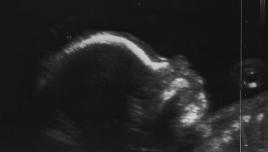

-------------------------------------------------------------------- 01.02.2006 --------------------------------------------------------------------

"Wir" sind nun im 5. Monat und durften uns nach dem letzten Ultraschall ganz tolle Bilder von unserem Kleinen betrachten. xxx (Name steht immer noch nicht fest und Vorschläge werden gerne entgegen genommen) mißt  nun stolze 21cm und sein Näschen und die Kopfform sind ganz sein großer Bruder.